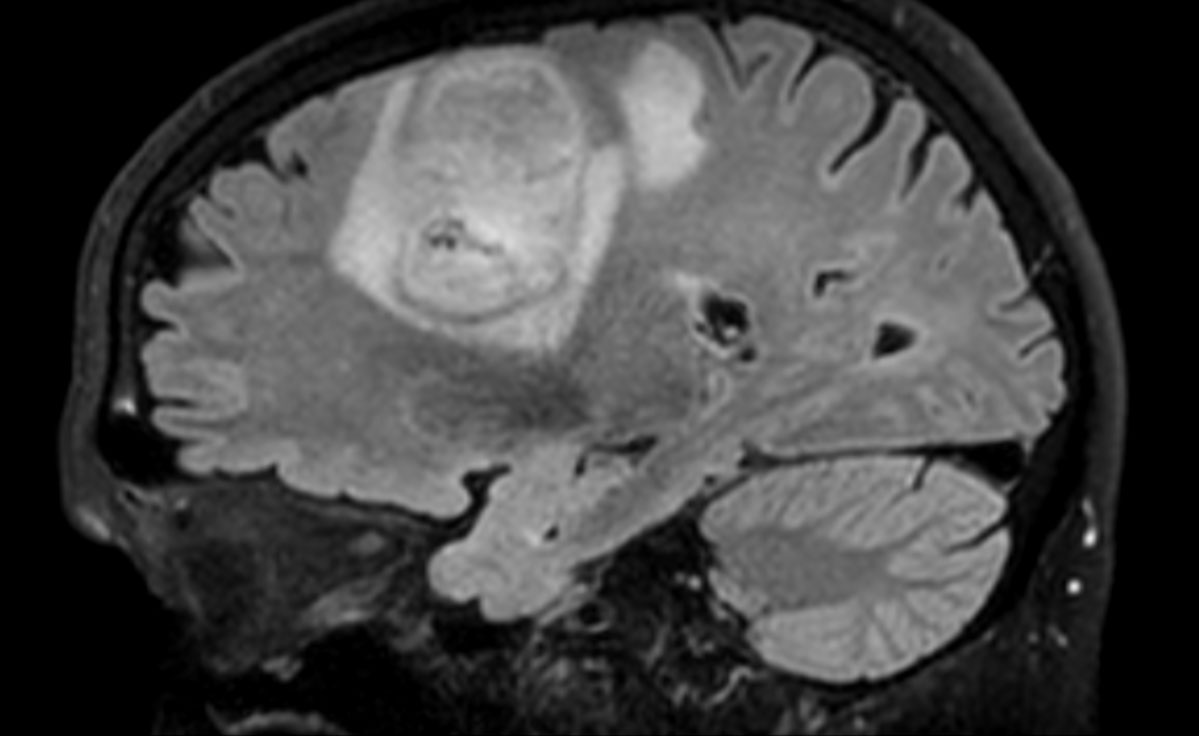

3D T1w TFE (sagittal reformat)

-

3D T1w TFE with gado (sagittal reformat)

Previous